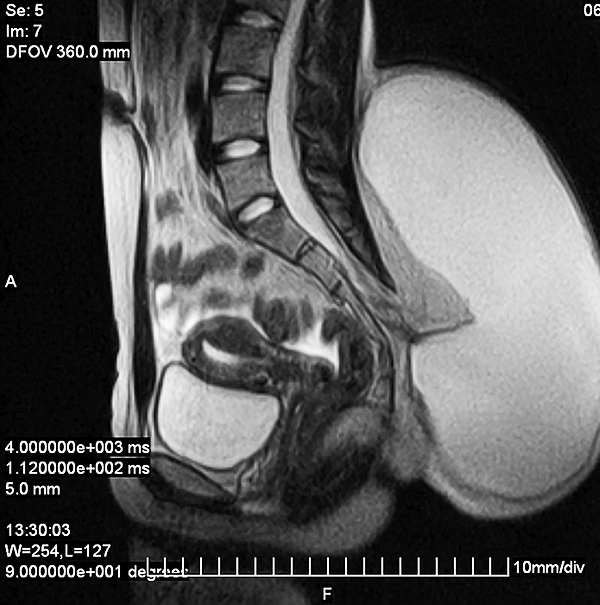

Presentamos un segundo paciente, perteneciente al grupo 2, de una paciente adulta joven, de 19 años, con antecedentes de una pequeña tumoración lumbar de aproximadamente 1.5 cm de diámetro que refiere tener desde el nacimiento (patología congénita). Refiere tener un crecimiento paulatino de dicha lesión hasta alcanzar un diámetro aproximado de 12 cm a los 18 años. Durante el siguiente año, la paciente consulta por presentar dicha tumoración de aproximadamente 25 cm de diámetro, la cual había aumentado de tamaño en asociación a un proceso infeccioso local secundario a un traumatismo leve en esa región (figs. 2 y 3). Se confirma el diagnóstico de un lipomeningocele y se le solicitan los estudios pertinentes. Se decide la intervención quirúrgica de la lesión, reparando el defecto mediante la exéresis de la pared del meningocele, con formación de un nuevo fondo de saco dural (figs. 4 y 5). La paciente evoluciona favorablemente, sin presentar síntomas de médula anclada al momento.

Figura 2: Lipomeningocele lumbar congénito.

Figura 3: Corte sagital de secuencia T2 del lipomeningocele: imagen prequirúrgica.